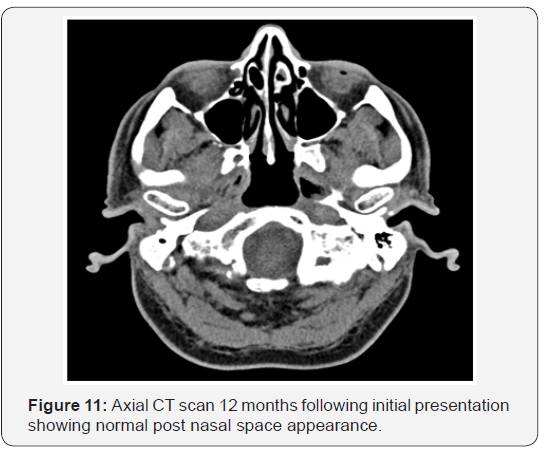

As the patient’s symptoms persisted and inflammatory markers increased, he underwent a repeat CT scan (Figure 4). The repeat scan showed bony erosion around the clivus and foramen lacerum. The findings necessitated a second examination under anaesthesia. Again a friable postnasal ulcer with granulations and pus was noted (Figure 5). Repeat biopsies were taken which were reported as granulation tissue and inflammation with amyloid deposition on the basis of special stains (Figures 6-9). Detailed clinical evaluations failed to demonstrate any evidence of systemic amyloidosis. The patient underwent repeated debridement of the ulcer under endoscopic guidance followed by intravenous antibiotics (meropenem) for six weeks and then oral trimethoprim for 4 months. Gradually the inflammatory markers improved and clinically his condition resolved over 6 months. The last clinical photograph taken at 12 months (Figure 10) showed healthy postnasal space mucosa with no signs of any recurrent disease. The last CT scan also taken at 12 months following initial presentation is shown in Figure 11.